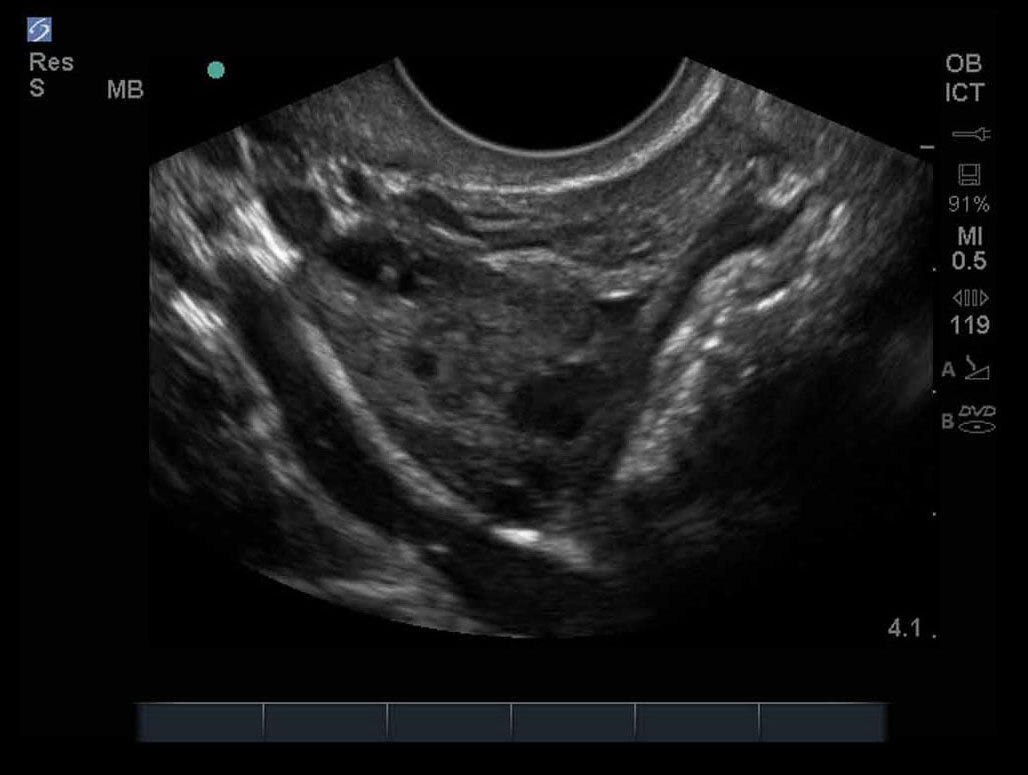

女性の骨盤10画像

M-Turbo:ICT 卵巣4。